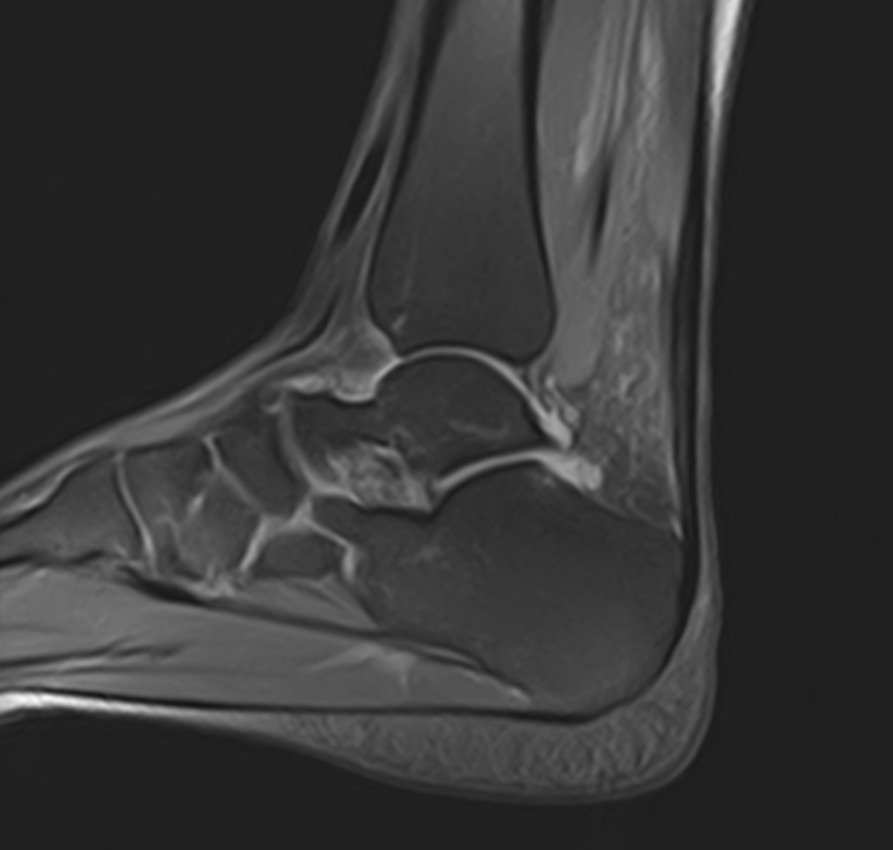

Наиболее точным и достоверным методом диагностики заболеваний голеностопного сустава является магнитно-резонансная томография. МРТ дает максимально полную информацию о состоянии всех анатомических структур сустава, включая костную ткань, сухожилия, связочный аппарат, нервные волокна и прилежащие мягкие ткани. Кроме высокой информативности метод МРТ является достаточно быстрой и безболезненной процедурой, при этом отличается безопасностью (нет рентгеновского облучения) и доступной ценой.

В нашей клинике можно пройти МРТ голеностопного сустава на современном высокопольном томографе экспертного класса TOSHIBA VANTAGE TITAN 1,5 Тесла, обладающего превосходной разрешающей способностью и создающего изображения с высокой детализацией и точностью.

Что покажет МРТ голеностопного сустава?

Снимки МРТ голеностопа показывают широкий спектр суставных заболеваний, включая:

• абсцесс и артрит, ахиллесов тендинит;

• трещины костей сустава и переломы;

• все разновидности костных инфекций;

• надрывы, растяжения и травмы сухожилий и хрящей;

• повреждение мышц голеностопа, остеонекроз (аваскулярный некроз);

• разрыв подошвенной фасции, дисфункции сухожилий;

• разрыв ахиллова сухожилия в области лодыжки;

• злокачественные и доброкачественные новообразования костных или мягких тканей;

• ущемление нервов, деформации, подагру, артроз;

• нарушение кровообращения в сосудистом русле сустава.